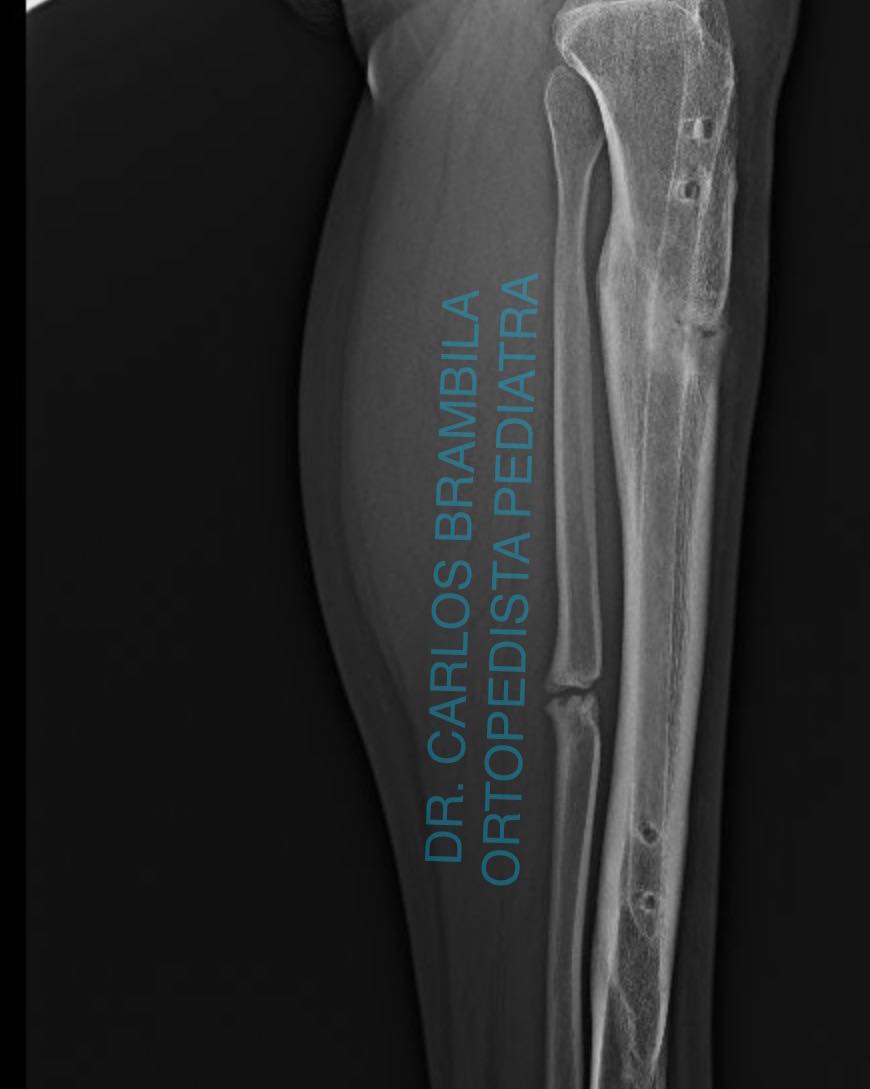

Hoy es un día especial y quiero aprovechar para compartir el caso de Emiliano, un joven de 17 años originario de Nayarit. Emiliano acudió conmigo por una deformidad en su pie, la cual había sido tratada quirúrgicamente en varias ocasiones sin éxito. Iniciamos un tratamiento con yesos, seguido de una cirugía para el balance neurológico del pie. Ahora, después de 5 meses, este es el resultado: Emiliano ya no necesita bastón para caminar y puede vivir libre y feliz.